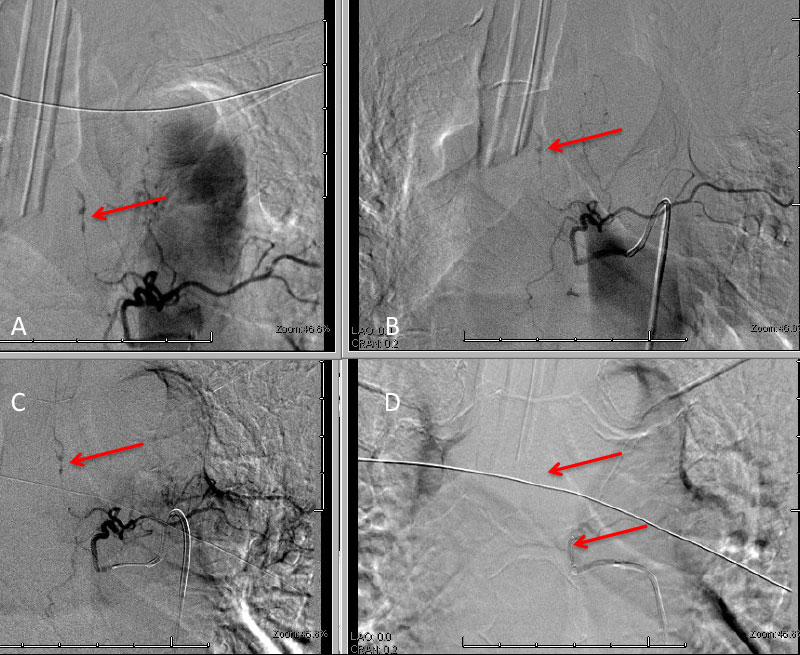

His initial angiogram excluded an underlying aneurysm or high flow arterial venous malformation of the brain, however a dissecting aneurysm of the left T5 pedicle was malformation of the brain, however a dissecting aneurysm of the left T5 pedicle was identified extending into the left T4-T5 left paramedullary space (Figure 3. A).

Figure 3: A) Initial left T5 DSA; B) 5 days post; C) Microcatheter DSA D) Post Coil Embolization demonstrating aneurysm obliteration

A selective WADA test of the left T5 pedicle with Brevital and lidocaine was performed and demonstrated loss of motor and sensory signal on intraoperative monitoring within the left lower extremity suggesting that this dissecting aneurysm of left T5 did have some contribution to the anterior spinal axis at this level. After initial discussions of options, we decided to initially place him on medical therapy with aminocaproic acid (72 hours), bed rest, and hemodynamic control of his blood pressure in the efforts to allow the aneurysm dissection to heal and potentially spontaneously thrombose. In addition, we volume expanded him in efforts to develop collaterals in the event that embolization of this dissection was required. A follow-up angiogram performed 5 days later demonstrated that the dissection did not thrombose and appeared very similar to the initial angiogram (Figure 3. B) and felt to represent a high risk for recurrent hemorrhage. We had extensive discussions with the patient and his spouse, who were prepared for potential difficult decisions regarding treatment of this high-risk lesion. Based on our judgment, we felt that the risks of recurrent hemorrhage were significant and that embolization of the feeding pedicle of left T5 should be performed to decrease the risk of potentially life-threatening or paralyzing disabling hemorrhage. We performed a coil embolization of the left T5 pedicle at the origin of the spinal artery, with the intention that collateral perfusion of the spinal cord would be achieved by adjacent healthy pedicles (Figure 3. C and D). He tolerated the procedure very well without adverse events or new neurologic deficits. We maintained the patient in the neuro ICU on bedrest with permissive hypertension and anticoagulation for 24-48 hours to encourage collateralization. After an additional 2 days of mobilization and observation, and a follow MRI demonstrating improved myelopathic signal and resolving focal left T4 hemorrhage, he was discharged home neurologically intact in good condition. Over the hemorrhage, he was discharged home neurologically intact in good condition. Over the next 6 weeks, his symptoms of abdominal and back pain resolved, and he regained all of his activities of daily living without limitation or neurologic deficits.